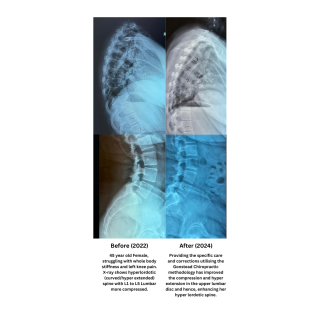

The Enhancement of Spinal Structural Integrity

Hyperlordosis (Hyperextension) of Lumbar Spine